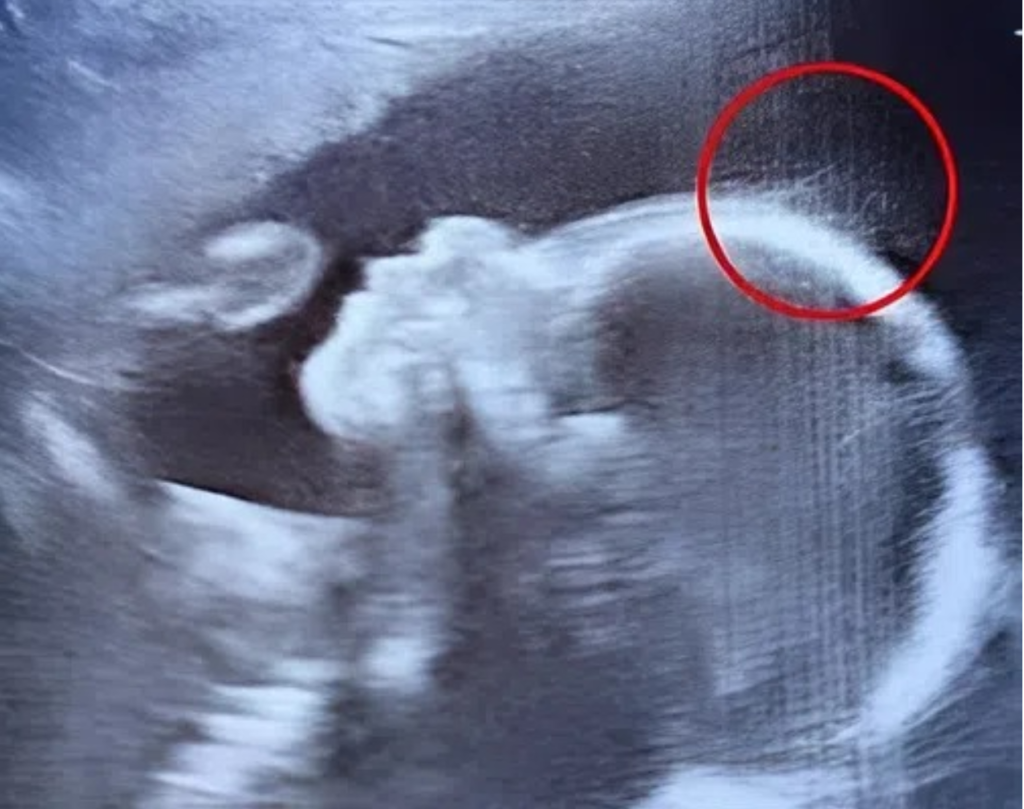

When Emily Foster walked into her 20-week pregnancy scan at the hospital, she expected a routine checkup. But what unfolded on the screen left everyone in awe. The technician’s eyes widened as she exclaimed, “Wait a second… is that hair?” Emily blinked in disbelief, and the doctor chimed in with a half-joking remark: “Looks like…